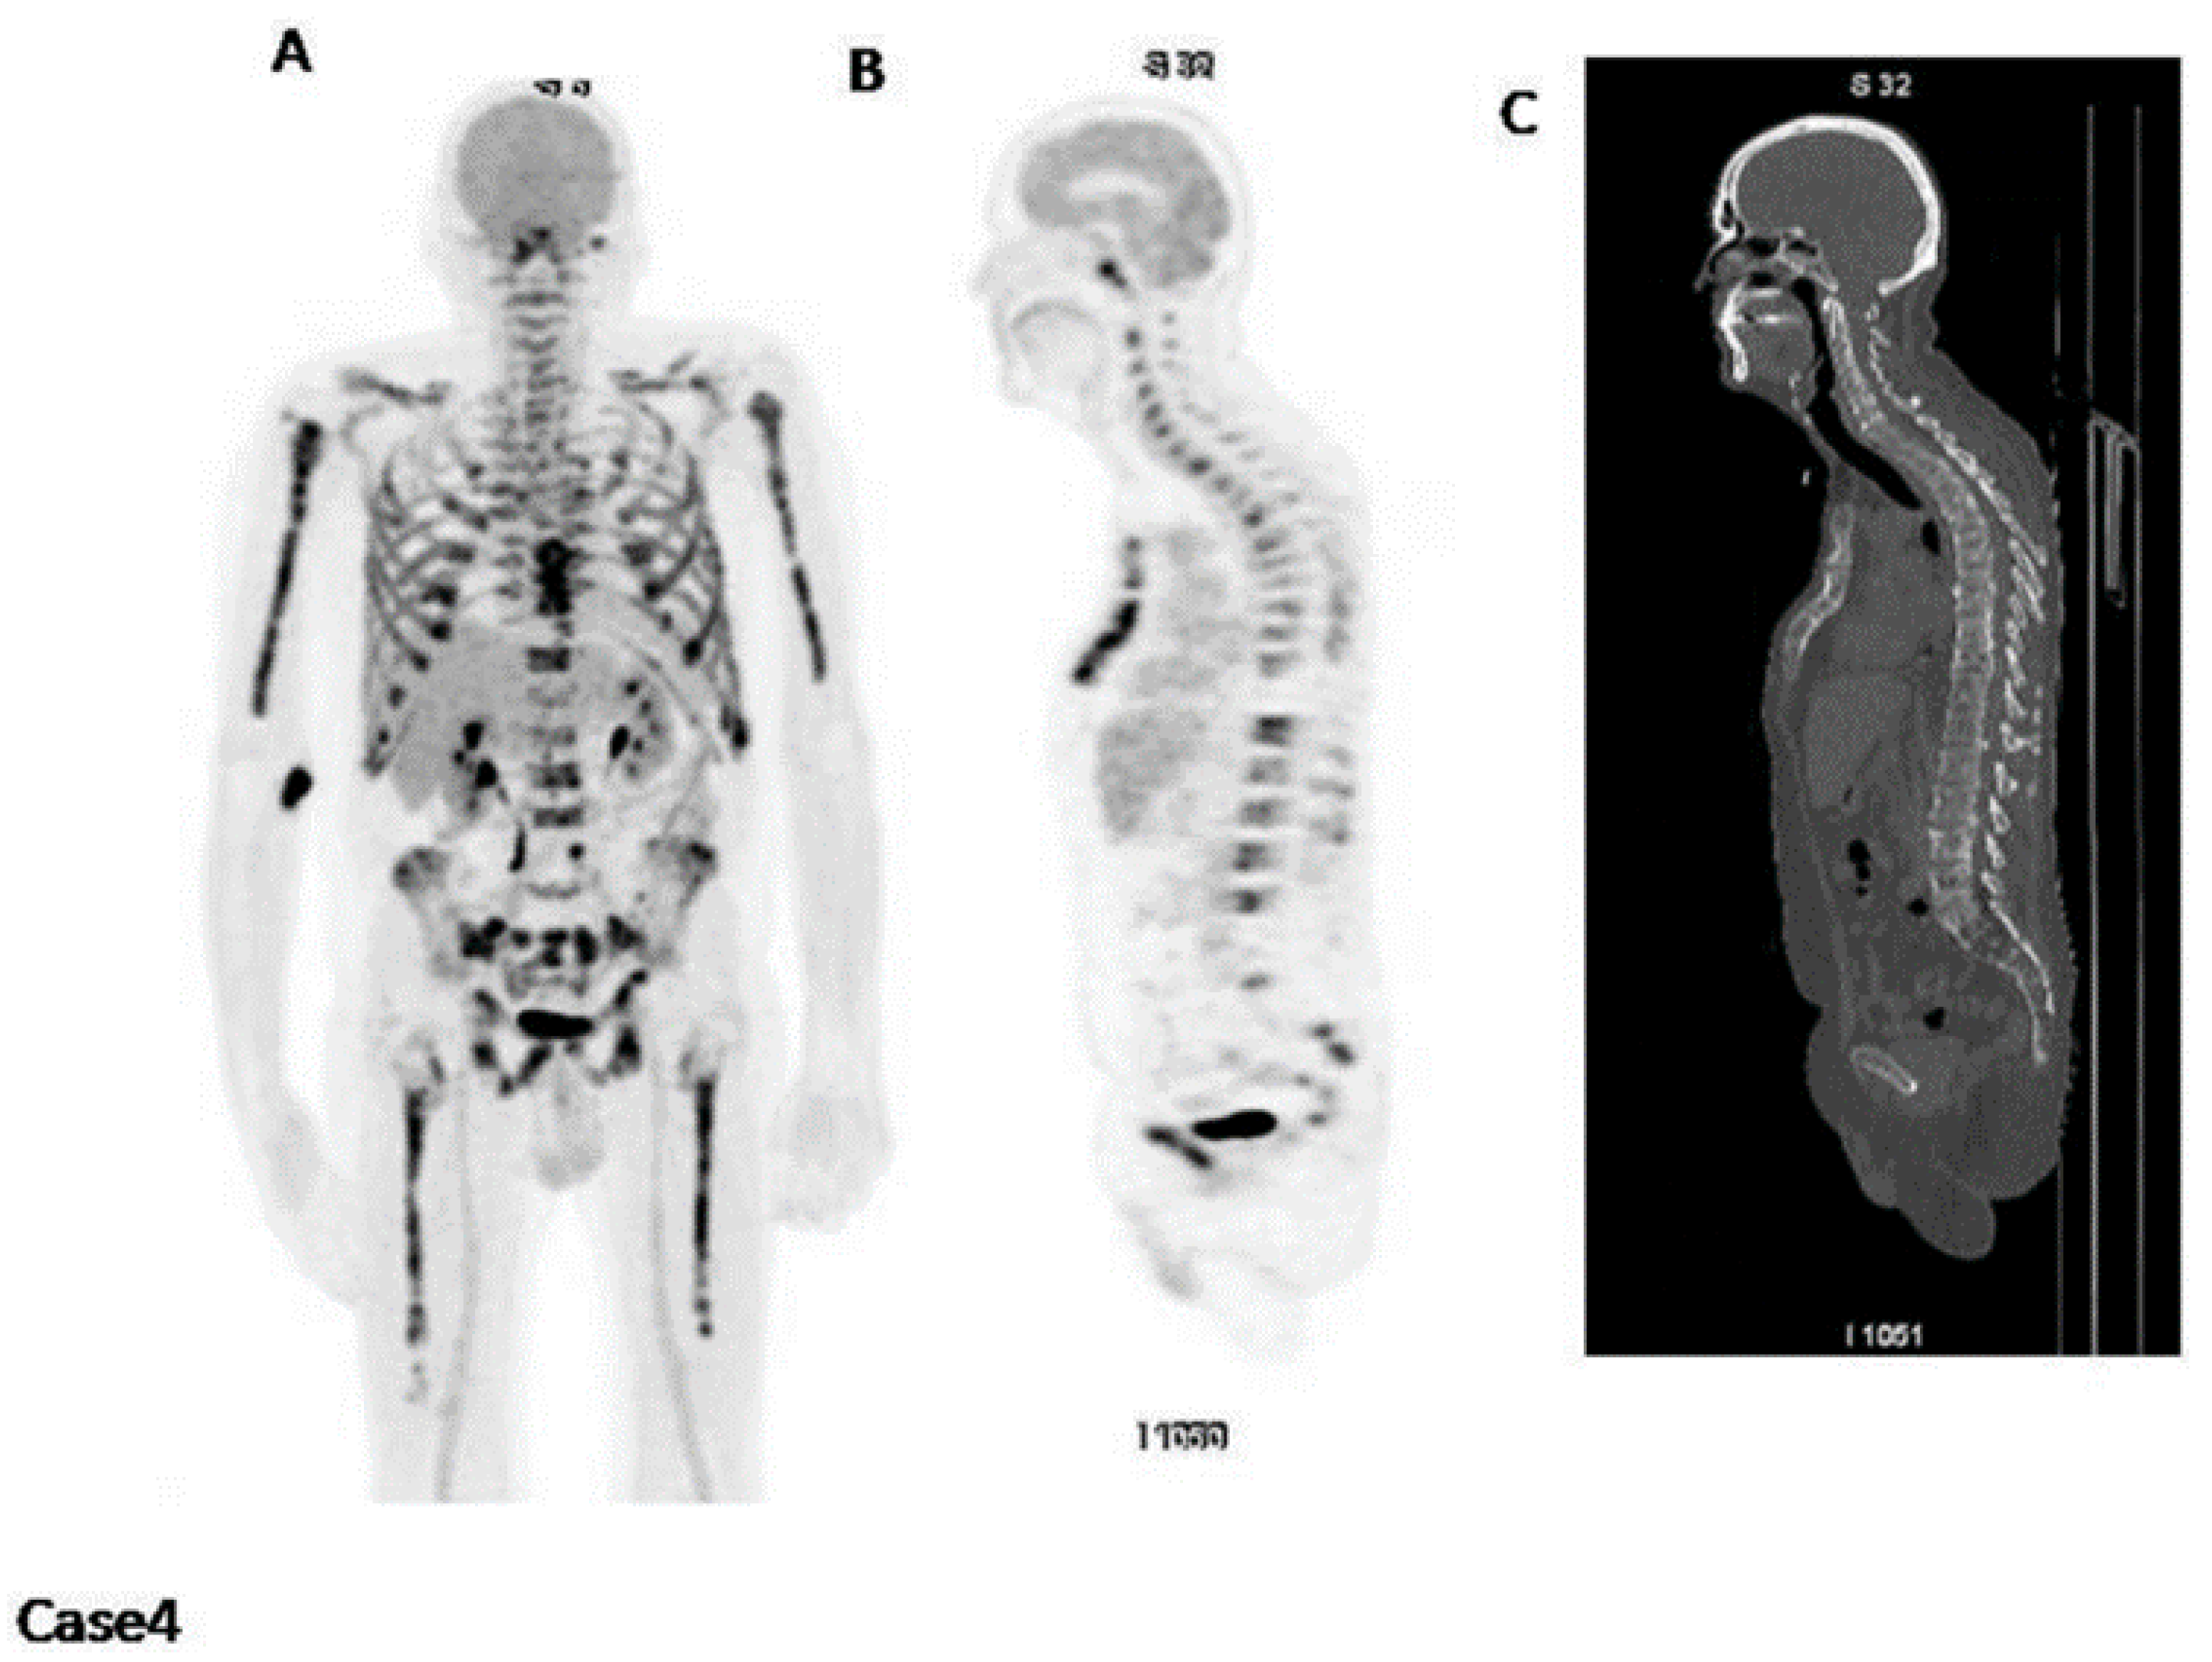

2. Assessment of Bone Disease in MM: An Examination of Osteolytic Lesions

4. Importance of [18F]FDG PET/CT in Assessing Treatment Efficacy

4.2. Assessment of Myeloma Patients after Treatment

8. PET for Assessment of Bone Turnover in Myeloma Patients